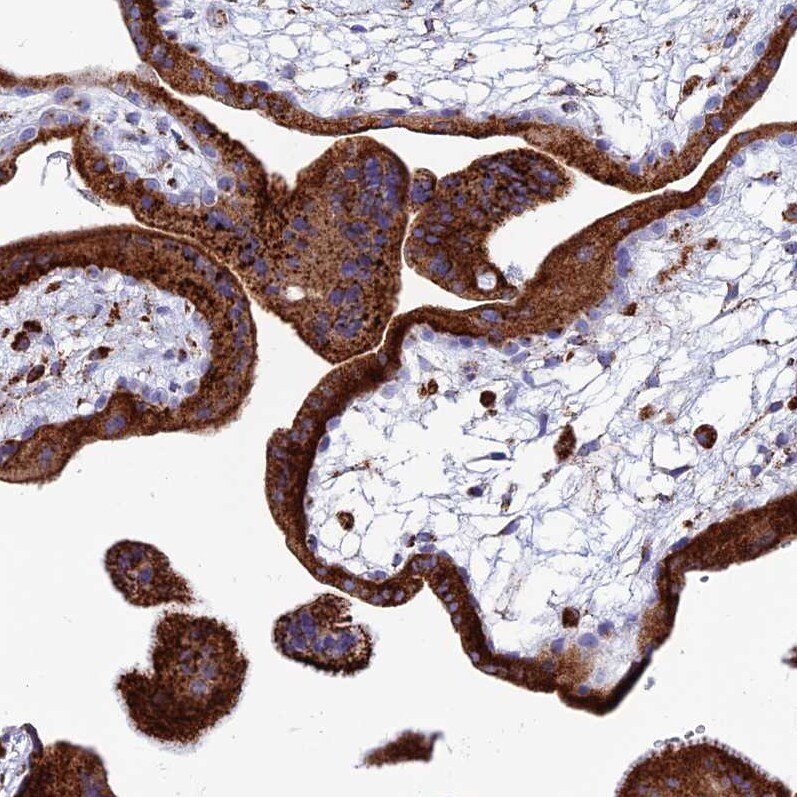

- Immunohistochemical analysis of SPNS1 in human placenta using SPNS1 Polyclonal Antibody (Product # PA5-59813) shows strong granular cytoplasmic positivity in trophoblastic cells.